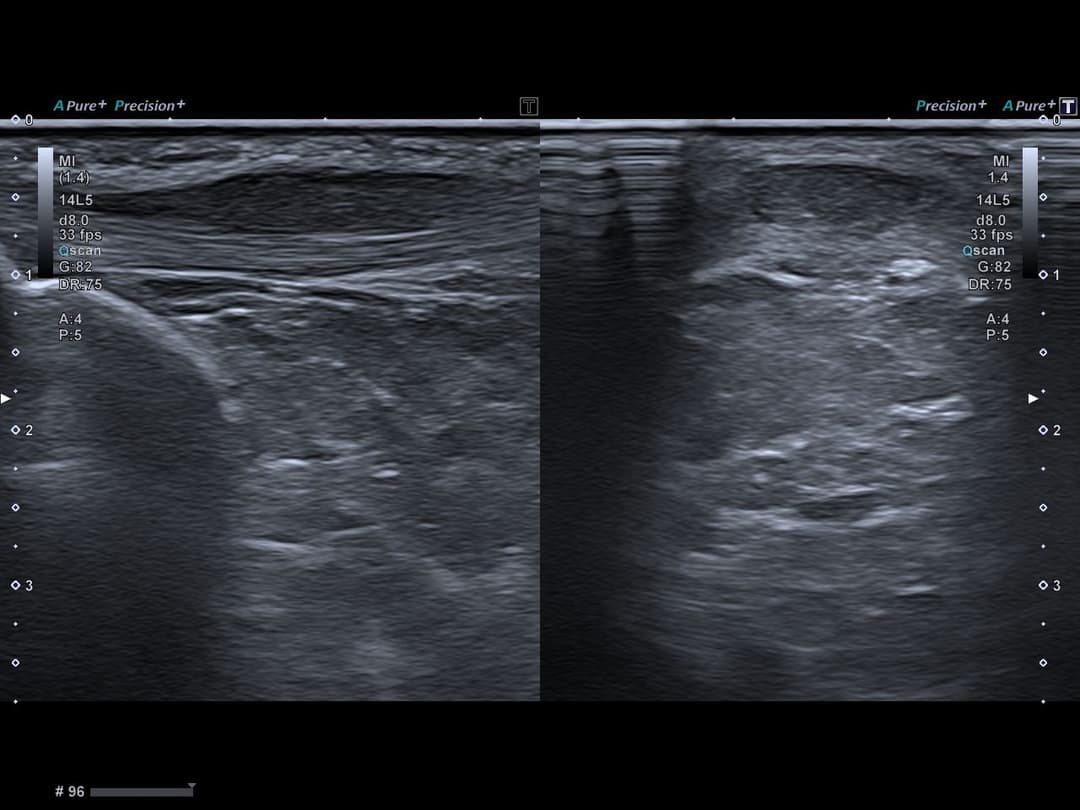

Tendinopathie patellaire corporéale superficielle

Échographie

Epaississement fusiforme avec hypo échogénicité de la portion corporéale superficielle du tendon patellaire, étendue sur 3cm de hauteur, sans fissuration intra-tendineuse notable.

Discret œdème des tissus mous cellulo-graisseux sous-cutanés adjacents.